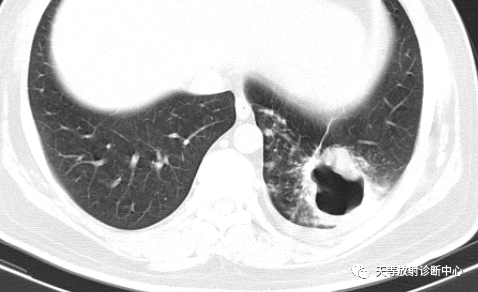

▲胞内分枝杆菌肺病,左肺上叶空洞。

▲胞内分枝杆菌肺病,小叶中心结节(树芽征)

▲胞内分枝杆菌肺病,小叶中心结节(树芽征),双肺多发厚壁空洞。

3、空洞是4个菌种组中常见的CT征象,空洞是由支气管壁及周围炎症形成结节,管壁溃疡坏死后,坏死物经支气管排出后形成。堪萨斯分枝杆菌组出现空洞的比 例要明显高于其他3组,而且空洞更多见于右肺上叶。不同菌种组中空洞的好发部位有其特征性,空洞的发生部位对判断各菌种有一定意义。

▲NTM的厚壁空洞